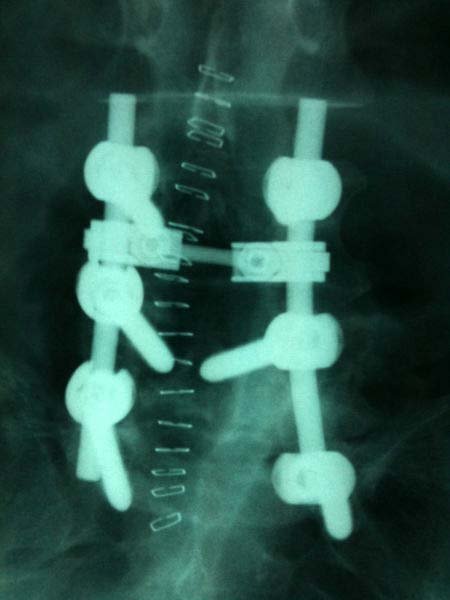

Yaşadığı sürekli bel ağrısı şikayetiyle hastaneye başvuran Ayten Dağlı isimli hastaya Ortopedi Uzmanı Dr. Ertuğrul Köseoğlu ve Beyin Cerrahi Uzmanı Dr. Salih Zeki İpekoğlu müdahele etti. Başarılı geçen operasyonun ilk etabında, kırık ve deforme olan omurga parçası çıkartıldı. Operasyonun ikinci kısımda da omurganın kaymasını önlemek için vida ile sabitleme yapılarak ameliyat başarıyla tamamlandı.